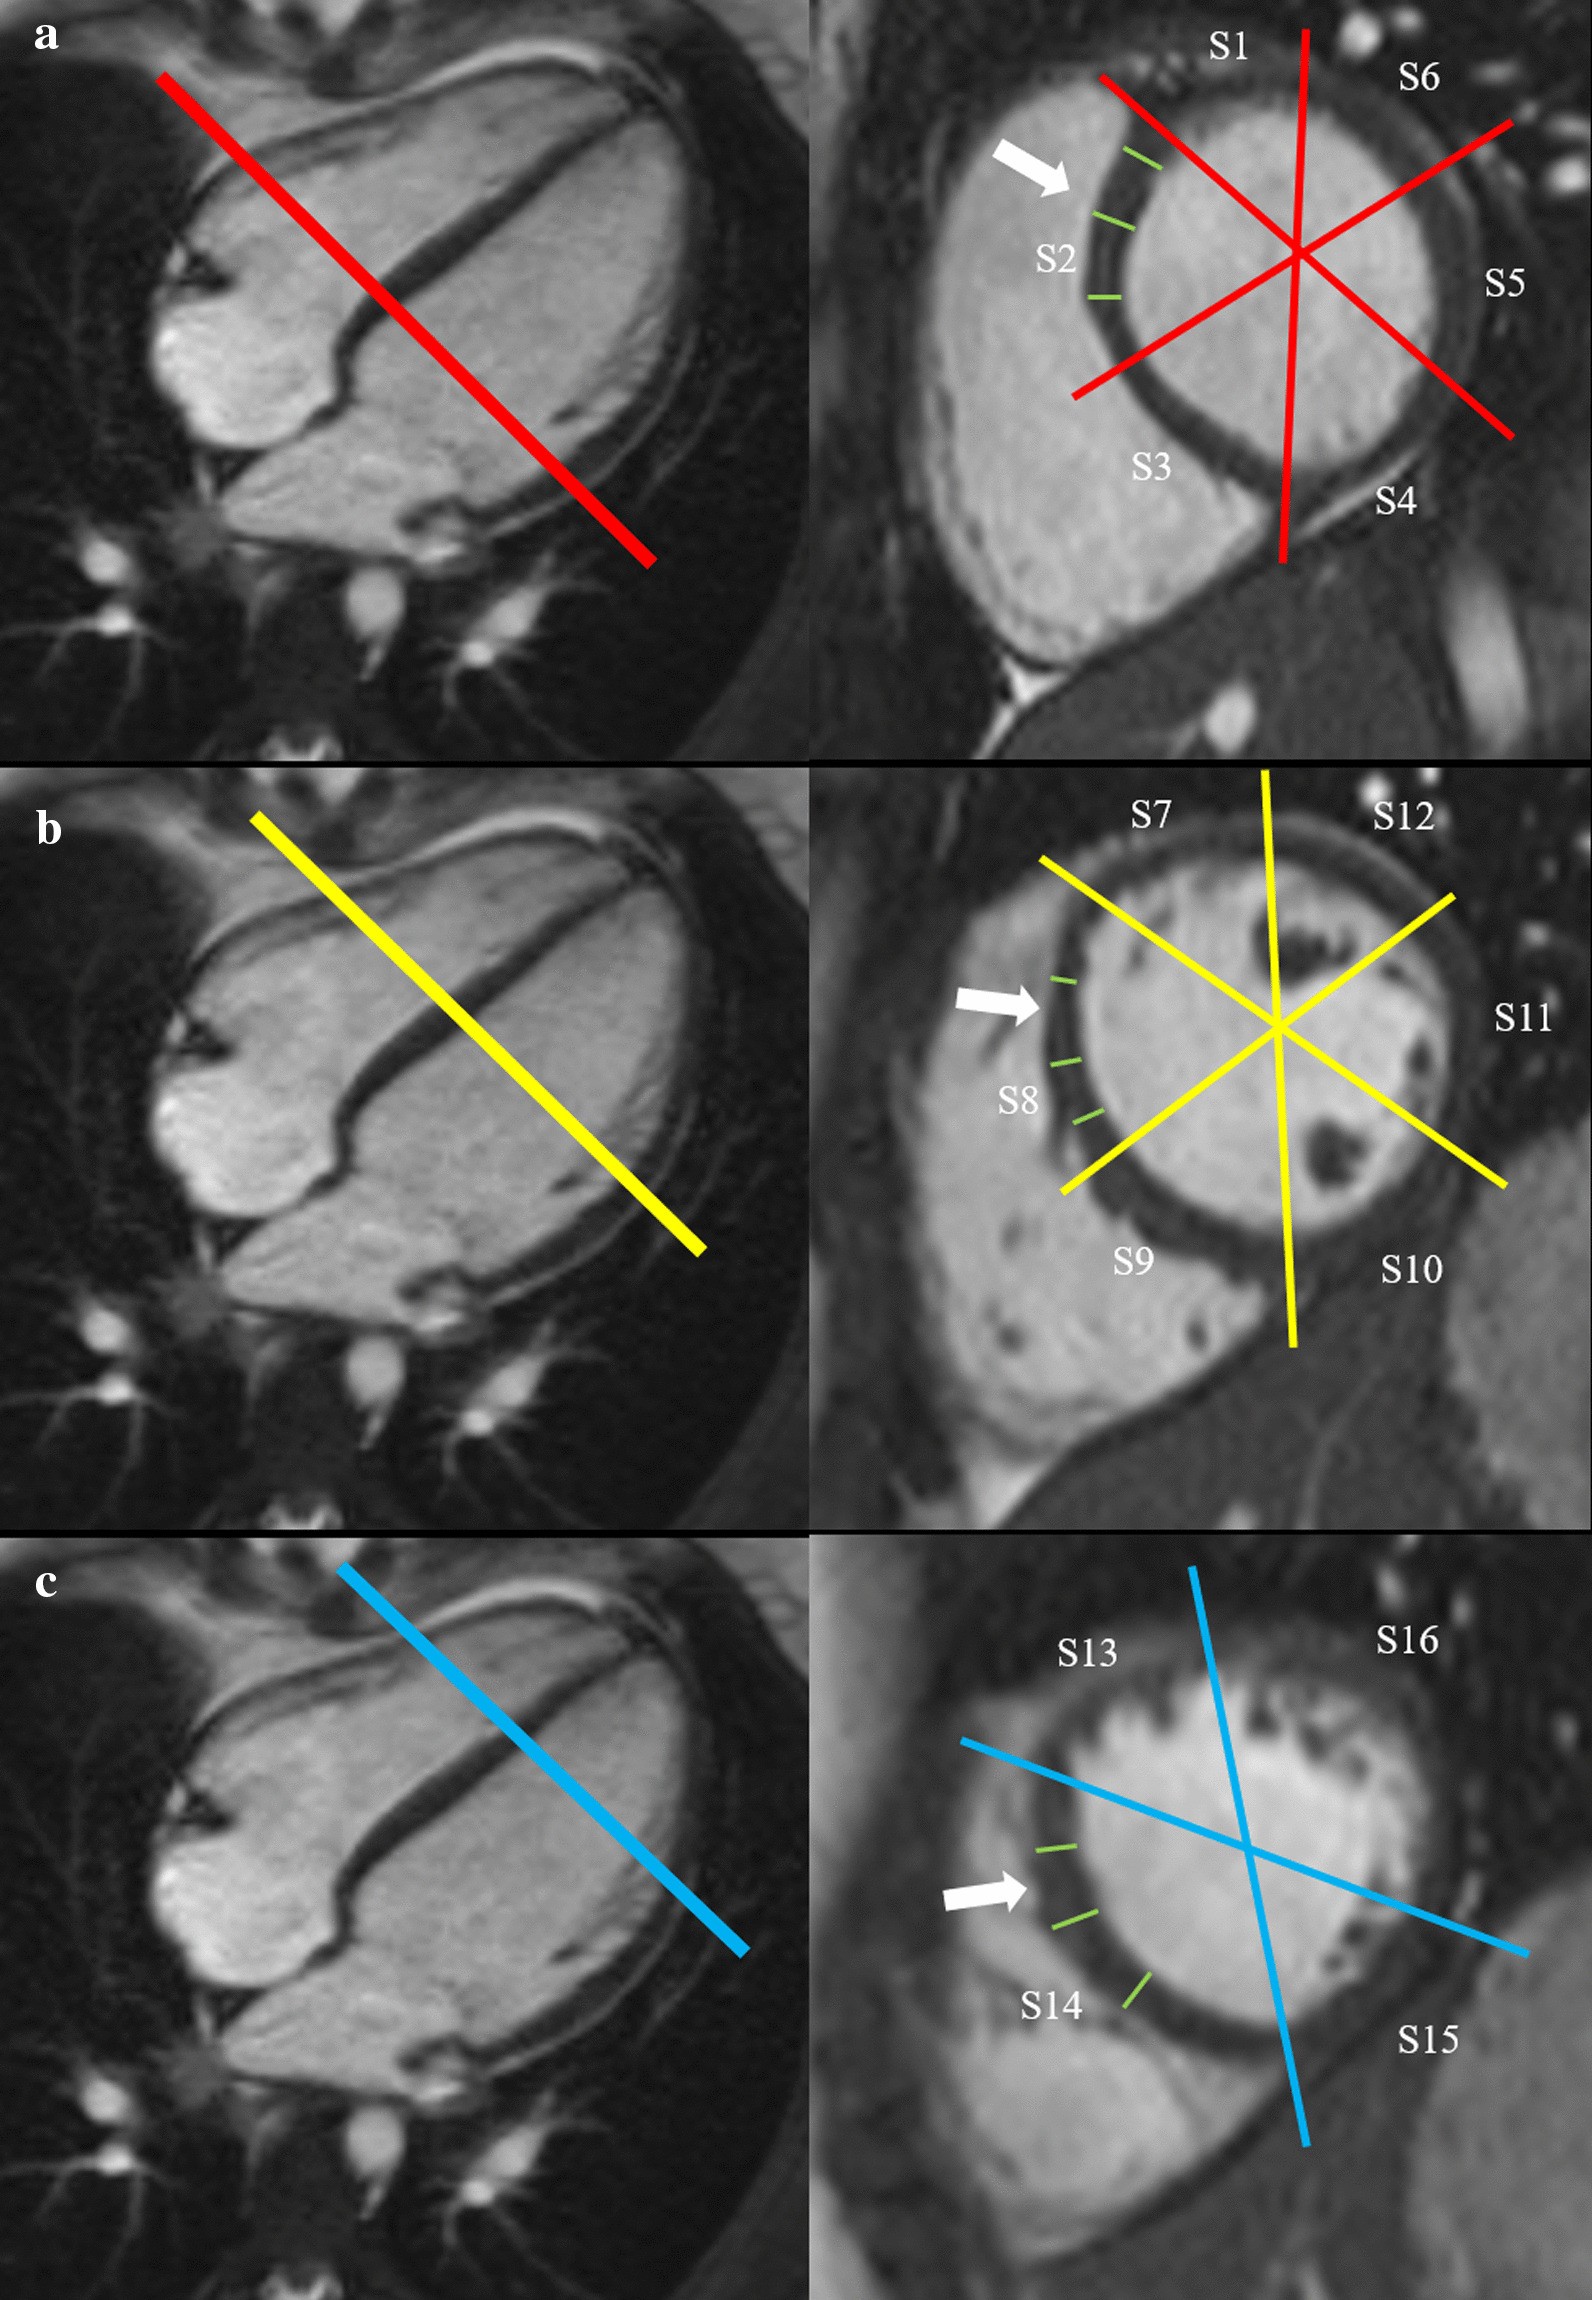

Fig. 1

Measurement of left ventricular (LV) myocardial thickness on short axis cine images at the end of diastole. First, the basal (a), mid-ventricular (b) and apical (c) level was defined. Second, all 16 segments (S1-S16) of the American Heart Association segmentation model were determined. And third, myocardial thickness was measured three times for each segment shown for segments S2, S8 and S14 (white arrows). S, segment